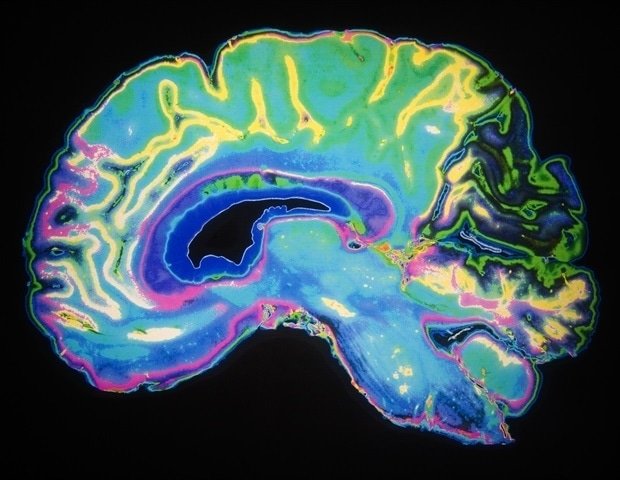

This paper focuses on the basal ganglia, a collection of neurons responsible for motor control and other roles. Of most interest to scientists is a small region called the substantia nigra, which controls movement and produces dopamine, among other functions. Scientists say the relationship between these structures and sleep, and how they relate to each other’s rhythms, has not been extensively studied until now.

“This study provides for the first time a detailed characterization of respiratory neural connections across multiple states, including rest-wake, non-REM sleep, REM sleep, and anesthesia, in the substantia nigra and primary motor cortex, which have not been studied previously.”” writes the author.

Scientists have found that there are nuances and differences in every state. One consistent thread, however, was that in the deepest non-REM sleep, breathing occurs almost independently of brain waves, with “slow delta” activity particularly evident in the deepest parts of sleep.

”The strength of respiratory and neural connections varied across multiple states, including NREM sleep, REM sleep, quiet wakefulness, and anesthesia, and was directly related to delta power, a characteristic of NREM sleep.” writes the author.